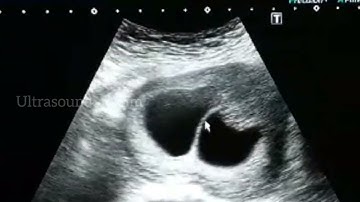

Lambda sign (twin peak sign) in twin pregnancy